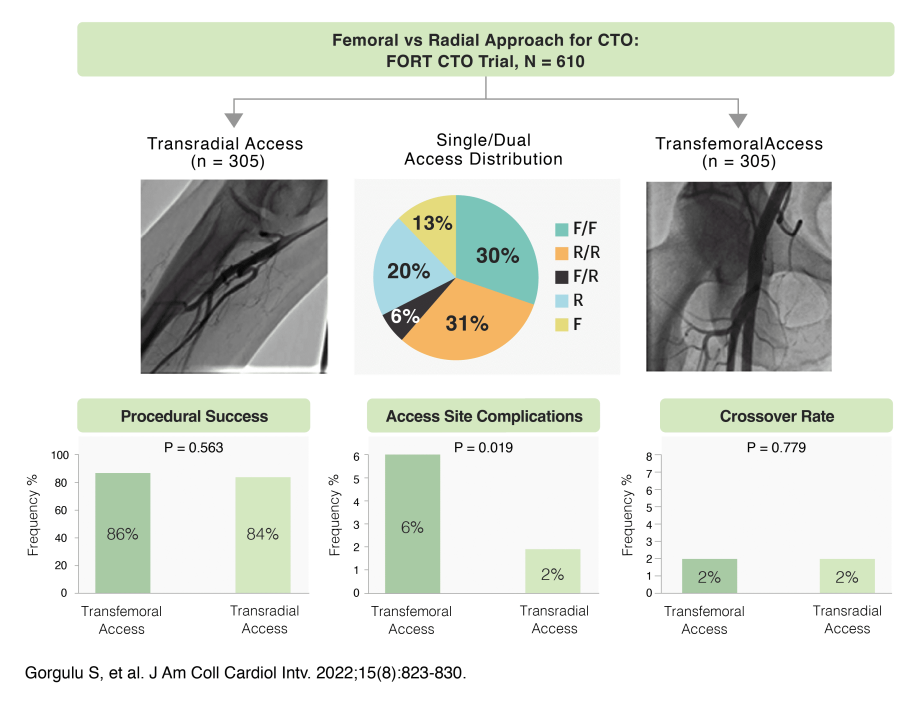

Many complex cases* traditionally

approached via femoral, are now

achievable with radial access.

*Complex cases: complex bifurcation,

left main, CTO, calcified vessel

Radial access is a viable option for

cases

where the femoral route

proves difficult.